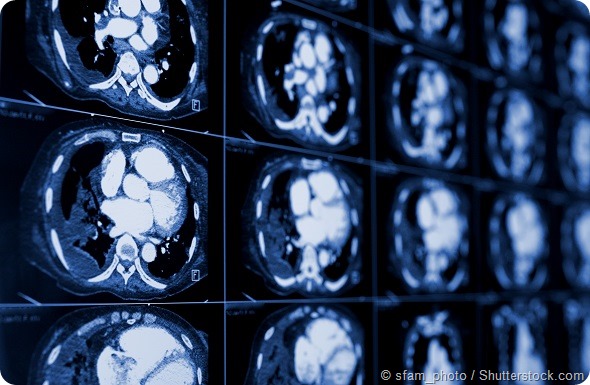

computed tomography of the chest. Medical background. monochrome photos

ILD is the result of inflammation and scarring in the lungs, and is one of the leading causes of death among people with systemic sclerosis. Gastrointestinal, heart and kidney involvement can also lead to substantial morbidity and mortality.

The presence of inflammation and scarring (fibrosis) in the lungs can result in an accelerated and progressive decline in lung function. As lung function declines, patients become more easily short of breath and generally require more and more supplemental oxygen in order to maintain normal oxygen levels in the blood.